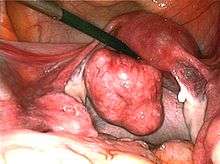

| Uterine fibroids as seen during laproscopic surgery | |